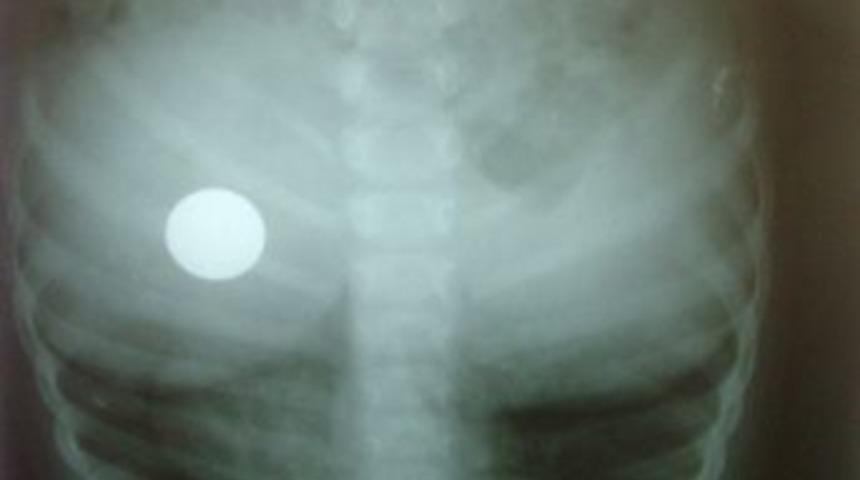

KONYA (İHA) - Konya'nın Kulu ilçesinde küçük bir çocuk, oyun oynarken eline geçirdiği madeni parayı yuttu.

Edinilen bilgiye göre, Alparslan Mahallesi'nde meydana gelen olayda Bülent K'nin 2 yaşındaki oğlu R.K, evlerinde ablası ile birlikte oyun oynadığı sırada eline geçirdiği 50 YKr'yi yuttu. Parayı yuttuğu sırada gözlerinden yaş geldiğini gören ablası durumu annesi ile babasına bildirdi. Ailesi tarafından Kulu Devlet Hastanesi'ne getirilen R.K'nin çekilen röntgeninde 50 YKr'nin midesinde olduğu tespit edildi. Paranın 24 saat içerisinde dışkı ile birlikte vücuttan atılacağını bildiren hastane yetkilileri,

ailelere de çocuklar oyun oynarken dikkatli olunması gerektiği uyarısını yaptı.